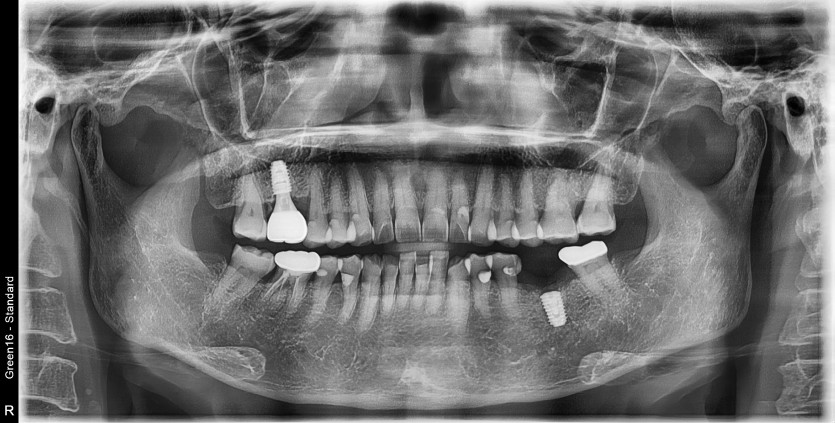

#36 타병원 임플란트 뼈이식 + 재식립